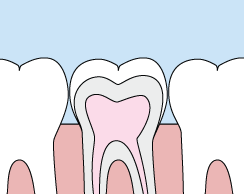

Crowns

Crowns are a restorative procedure used to improve your tooth’s shape or to strengthen a tooth. Crowns are most often used for teeth that are broken, worn, or have portions destroyed by tooth decay.

A crown is cemented onto an existing tooth that usually covers the portion of your tooth above the gum line. Essentially, the crown becomes your tooth’s new outer surface. Crowns can be made of porcelain, metal, or both. At Alamance Family Dentistry, we prefer porcelain crowns because they mimic the translucency of natural teeth and are very strong.

Crowns or onlays - partial crowns - are needed when there is insufficient tooth strength to hold a filling. Unlike fillings, during which the restorative material is applied directly into your mouth, a crown is fabricated away from your mouth. Your crown is created in a lab from your unique tooth impression, which allows a dental laboratory technician to examine all aspects of your bite and jaw movements.

The creation of a crown usually takes two appointments. During the first appointment, Dr. Dornblazer will prepare your tooth for your crown. This includes numbing the tooth, taking an impression, and placing a temporary crown for you to wear while our lab custom-creates your permanent crown. The process to create a permanent crown usually takes two weeks. During your second appointment, Dr. Dornblazer will remove the temporary crown and place the final crown.